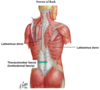

Latissimus dorsi

Origin : spinous processes of thoracic vertebrae below T6, thoracolumbar fascia, iliac crest and lower 3 or 4 ribs.

Insertion : intertubercular groove of the humerus.

Innervation : thoracodorsal nerve

Action : extends, adducts and medially rotates the upper extremity

Triangle of auscultation

Triangle of auscultation formed by the trapezius, rhomboid major and latissimus dorsi.